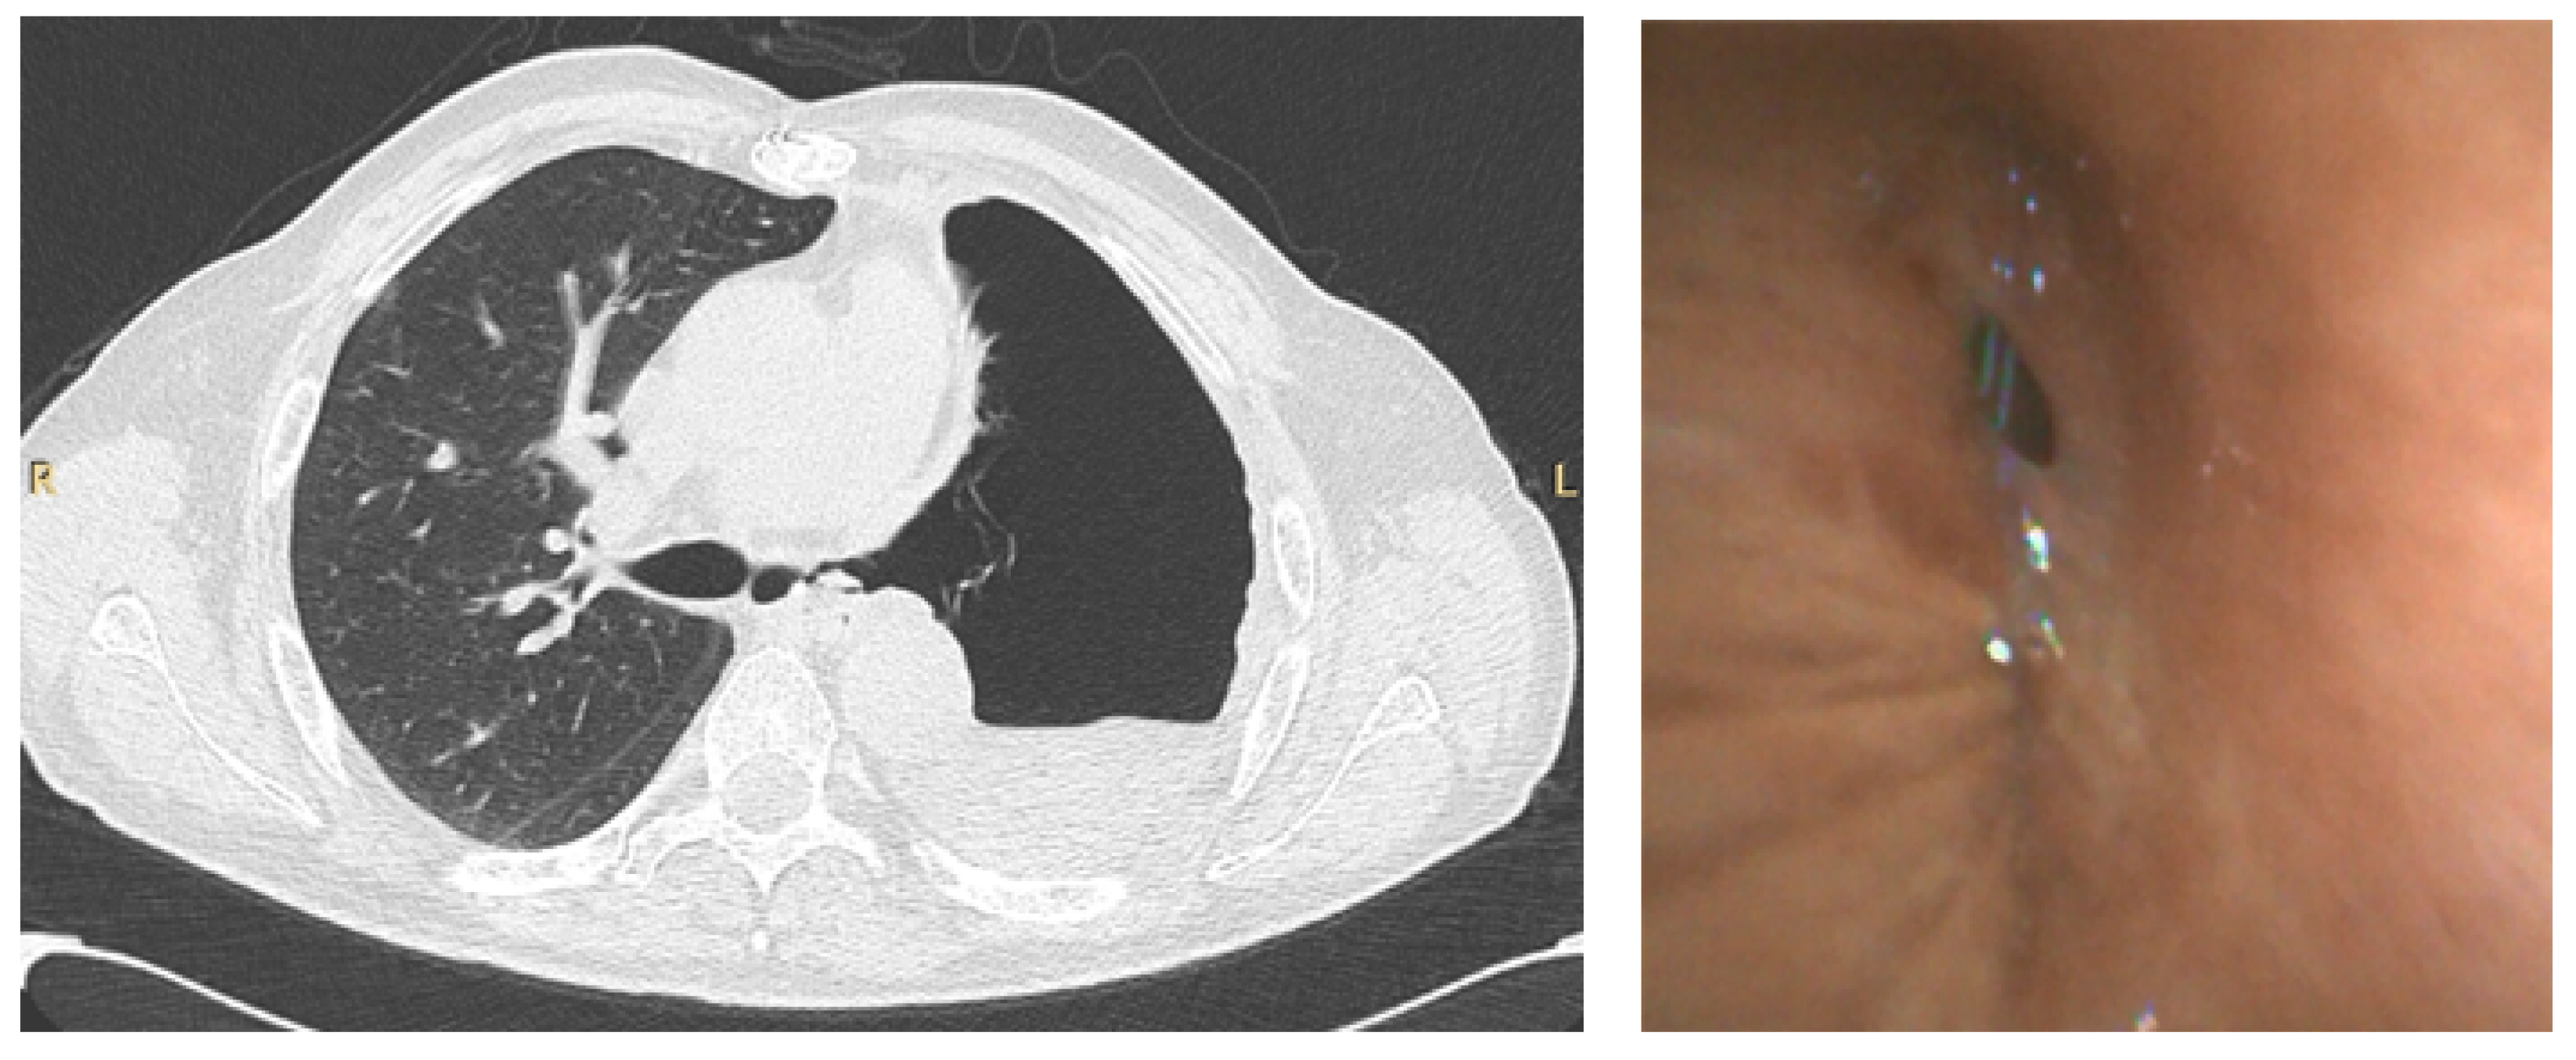

Bronchoscopy during the pandemic was also useful in other scenarios. In our institution, apart from the emergent/urgent indications mentioned above, we performed bronchoscopy in a patient with COVID-19 that underwent a left pneumonectomy for lung cancer, to investigate the presence of a bronchopleural fistula, which was confirmed, in order to decide the best therapeutic intervention (Figure 3).

CT scan (left) of a patient that underwent left pneumonectomy, showing a possible left bronchopleural fistula, in a COVID-19 positive patient, confirmed by bronchoscopy (right) using single-use flexible bronchoscope.